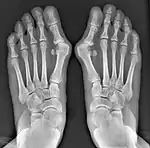

- For severe bunion deformity correction (Fig. 7)

- For recurrence correction after osteotomy procedure (Fig. 8)

Late deformity recurrence can happen after osteotomy (bone-breaking) procedures because osteotomy surgeries do not specifically stabilize first metatarsal bone.